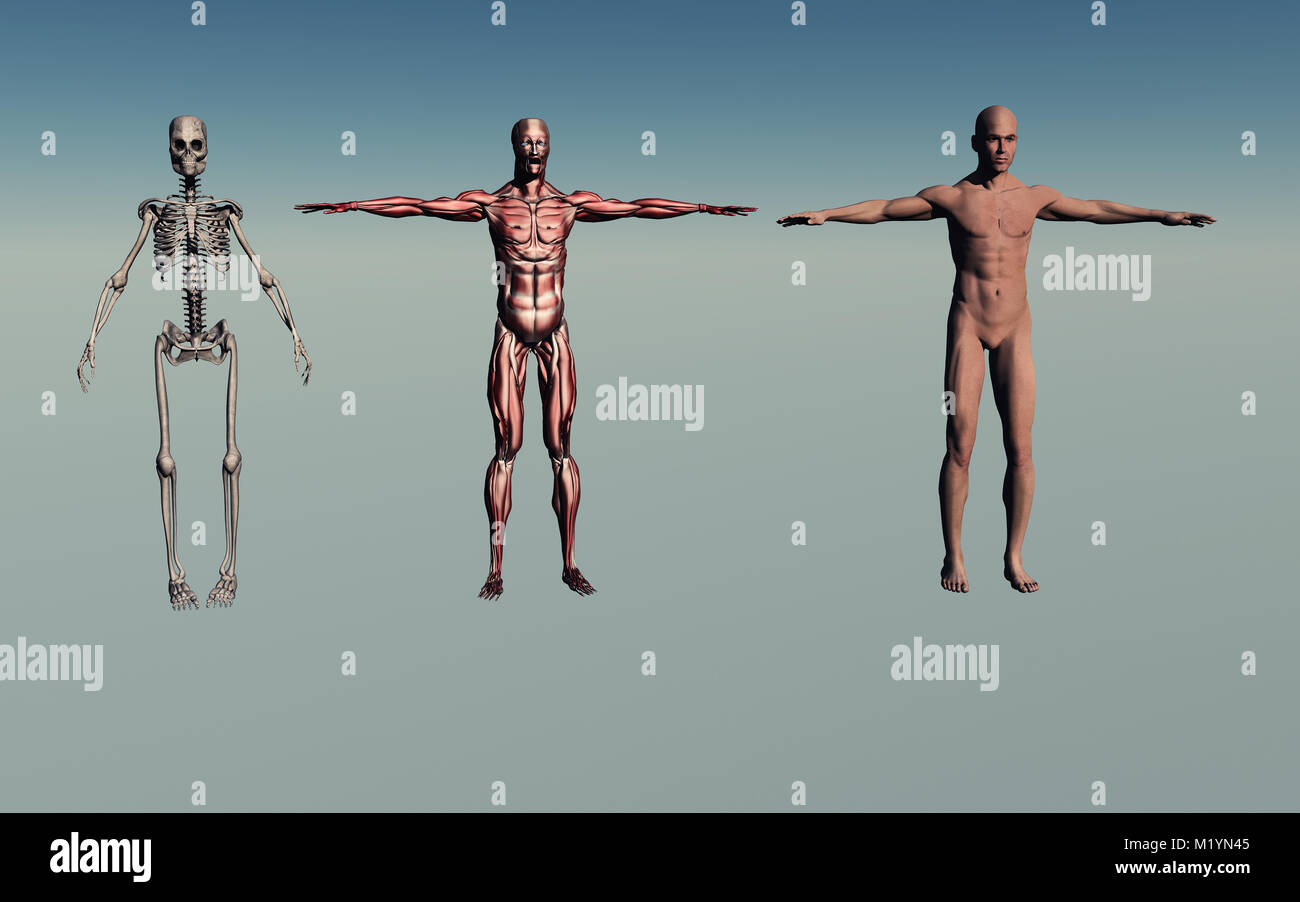

RMFX60TP–Menschen, Anatomie, Muskel, Körper, medizinische, Medizin, Illustration, Mann, Männlich, Gesundheit, muskulös, Wissenschaft, System, Biologie, Muskeln, ich

RF2A9AXYJ–Menschliche Körper Anatomie Muskeln Aufbau eines männlichen, Vorderansicht Seitenansicht und Perspektive, 3D-Rendering im Hintergrund

RF2A9AP5X–Menschliche Körper Anatomie Muskeln Aufbau eines männlichen, Vorderansicht Seitenansicht und Perspektive, 3D-Rendering im Hintergrund

RF2A9APDN–Menschliche Körper Anatomie Muskeln Aufbau eines männlichen, Vorderansicht Seitenansicht und Perspektive, 3D-Rendering im Hintergrund

RF2A9AX48–Menschliche Körper Anatomie Muskeln Aufbau eines männlichen, Vorderansicht Seitenansicht und Perspektive, 3D-Rendering im Hintergrund

RF2A9AXPX–Menschliche Körper Anatomie Muskeln Aufbau eines männlichen, Vorderansicht Seitenansicht und Perspektive, 3D-Rendering im Hintergrund